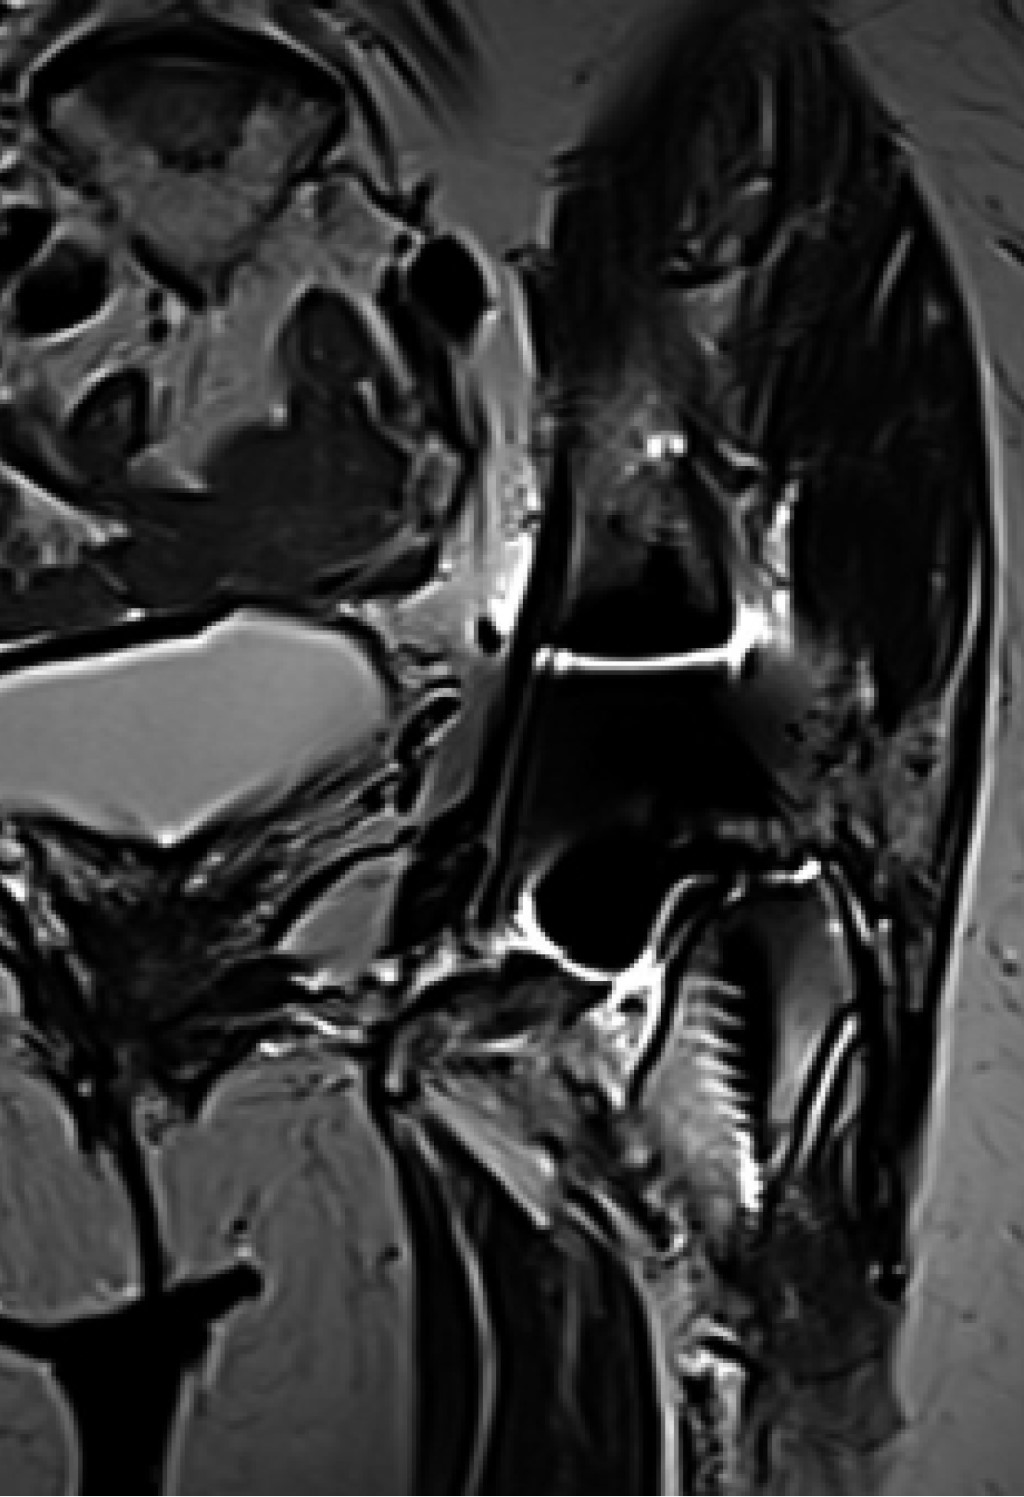

Como protocolo diagnóstico, se solicitó una radiografía anteroposterior de pelvis en la cual se observó el estado de los componentes protésicos sin cambios a comparación de la radiografía inicial posterior a la artroplastia total de cadera izquierda, con lo cual se descartó aflojamiento aséptico o fatiga del material (Figura 1). También una resonancia magnética no contrastada en la cual se observó tendinosis insercional del glúteo menor y avulsión > 50% anterior de la inserción del glúteo medio con infiltración grasa en menor cantidad a las fibras musculares de su vientre muscular (Figura 2).

Dentro de los estudios de gabinete que deben ser solicitados, se inicia con una radiografía anteroposterior de pelvis para descartar diagnósticos diferenciales, como alteración en la posición de los implantes y en el offset, así como datos de aflojamiento periprotésico.2 García y colaboradores describen el ultrasonido como un método fiable para detectar y medir la extensión de las rupturas de los tendones abductores; sin embargo, continúa siendo operador dependiente.3 La artrografía es un estudio poco específico para diagnosticar esta patología2 y la resonancia magnética es el estudio más sensible y específico para clasificar roturas de los tendones de los músculos abductores. En esta última, se pueden observar cambios de intensidad en las zonas de lesión y la presencia o no de degeneración grasa muscular. La única desventaja de la resonancia magnética es que puede llegar a sobreestimar el número de lesiones de aparato abductor cuando se correlaciona con la clínica.4

Figura 2